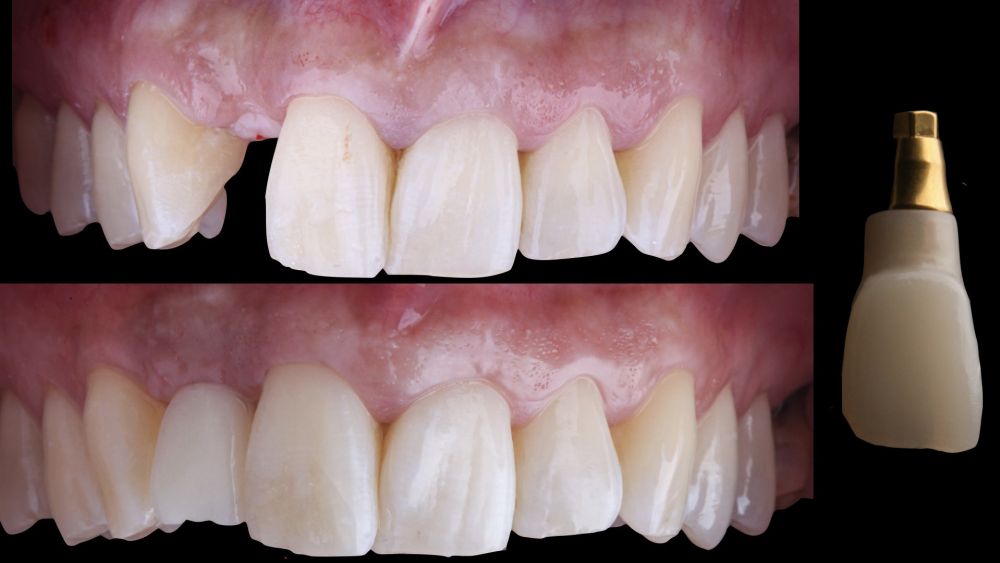

* Phase III: three months after implant placement, the soft tissue condition was favourable (Figures 5 and 6). A digital impression was obtained using an intraoral scanner for the fabrication of a screwretained

polymethyl methacrylate (PMMA) provisional restoration. Regarding the definitive

implant crown, a cement-screw-retained

restoration was fabricated with a titanium nitride interface, adapting the design to the emergence profile already consolidated with the provisional prosthesis. The crown was produced by CAD-CAM in zirconia with full reduction and feldspathic ceramic veneering for zirconia (Figure 7).